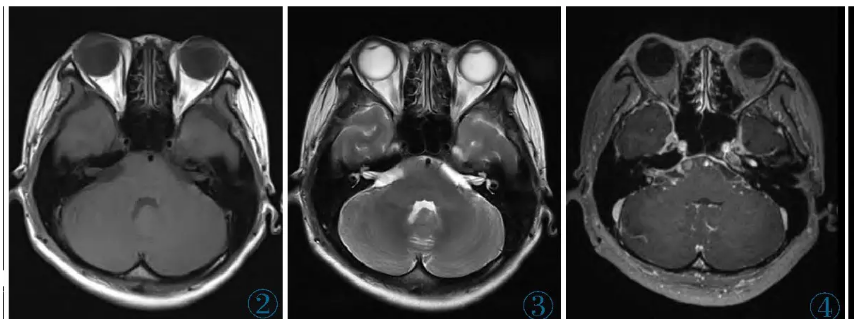

颅脑MRI示鞍上池、环池、侧裂池等区域的软脑膜呈弥漫性增厚、强化(图1),其中最大的结节凸向右侧桥脑前池,大小约11 mm×8 mm,呈宽基底与邻近脑膜相连,T1WI及T2WI呈等信号,增强扫描轻度强化,DWI未见弥散受限,PET-CT示该结节与脑膜病灶代谢轻度增高(图2~5)。脑室系统广泛扩张。左肺下叶外基底段可见数个实性小结节,边界清,直径约1~3 mm,代谢未见异常。

图2~4右侧桥脑前池内见一结节呈宽基底与邻近脑膜相连,T1WI及T2WI呈等信号,增强扫描轻度强化。